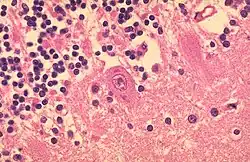

- TOUTON-Riesenzelle - Schaumzellen, bei denen um eine kleine schaumfreie Insel mehrere Kerne ringförmig angeordnet sind, Vorkommen z.B. bei juveniler Xanthogranulomatose, siehe Abb.

- Mehrkernige Riesenzellen - Sie entstehen durch Verschmelzung mehrerer Zellen oder bei inhibierter Zellteilung und kommen sowohl physiologisch als auch im Rahmen pathologischer Prozesse vor.

- Histiozytäre Zellen:

- Fremdkörper-Riesenzellen - Typisch in Fremdkörpergranulomen, die Zellkerne sind in einem Haufen zusammengelagert

- LANGHANS-Riesenzellen - In Tuberkulosegranulomen, die Kerne sind hufeisenförmig angeordnet

- ANITSCHKOW-Riesenzellen - Bei rheumatischer Myokarditis